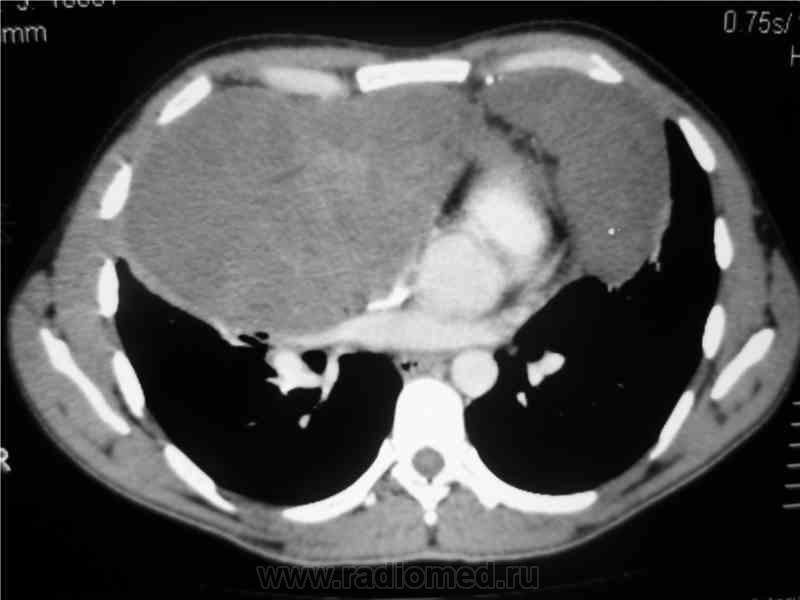

Мужчина 36 лет, рентгеногафия и КТ грудной полости.

Жалобы на субфебрильную температуру, боли в грудной клетке справа, слабость, похудание. ФГ 10 месяцев назад - норма.

КТ август 2009.

Интенсивное, однородное затемнение в средних отделах справа, слева норма - мною был заподозрен м/долевой плеврит, пациент был направлен в областной центр торакальной хирургии. Затем онкодиспансер, затем институт рака в Киеве. Результат гистологии тератобластома средостения. 2 курса химиотерапии контрольное КТ в октябре - отрицательная динамика.

Массивное неоднородное мягкотканное новообразование, исходящее из верхней или средней трети переднего средостения, оттесняет крупные сосуды вправо и кзади. По локализации должна быть злокачественная тимома. Хотя и лимфому наверное, не стоит отбрасывать, Ходжкинская маловероятна.